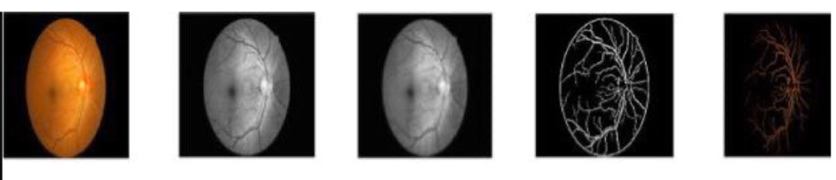

而在DR诊断中,常需要将血管、微动脉瘤、渗出物等特征分割出来,以便医生判断病情。(我们着重讲述分割血管。)

- 在眼底成像过程中,不同深度的视网膜结构投射到具有最大强度的二维图像上,会导致非血管结构的重叠,和低对比度图像中细血管的可见性降低。

- 成像会引入伪影、不均匀照明等不利因素。

- 中央凹、视盘、视网膜边界、硬性渗出物、出血和其他病理改变呈现出复杂的情况,需要考虑。

- 中央反射呈白色条带,通常位于动脉(上分支血管)的显著位置,可能会导致错误的分割过程。